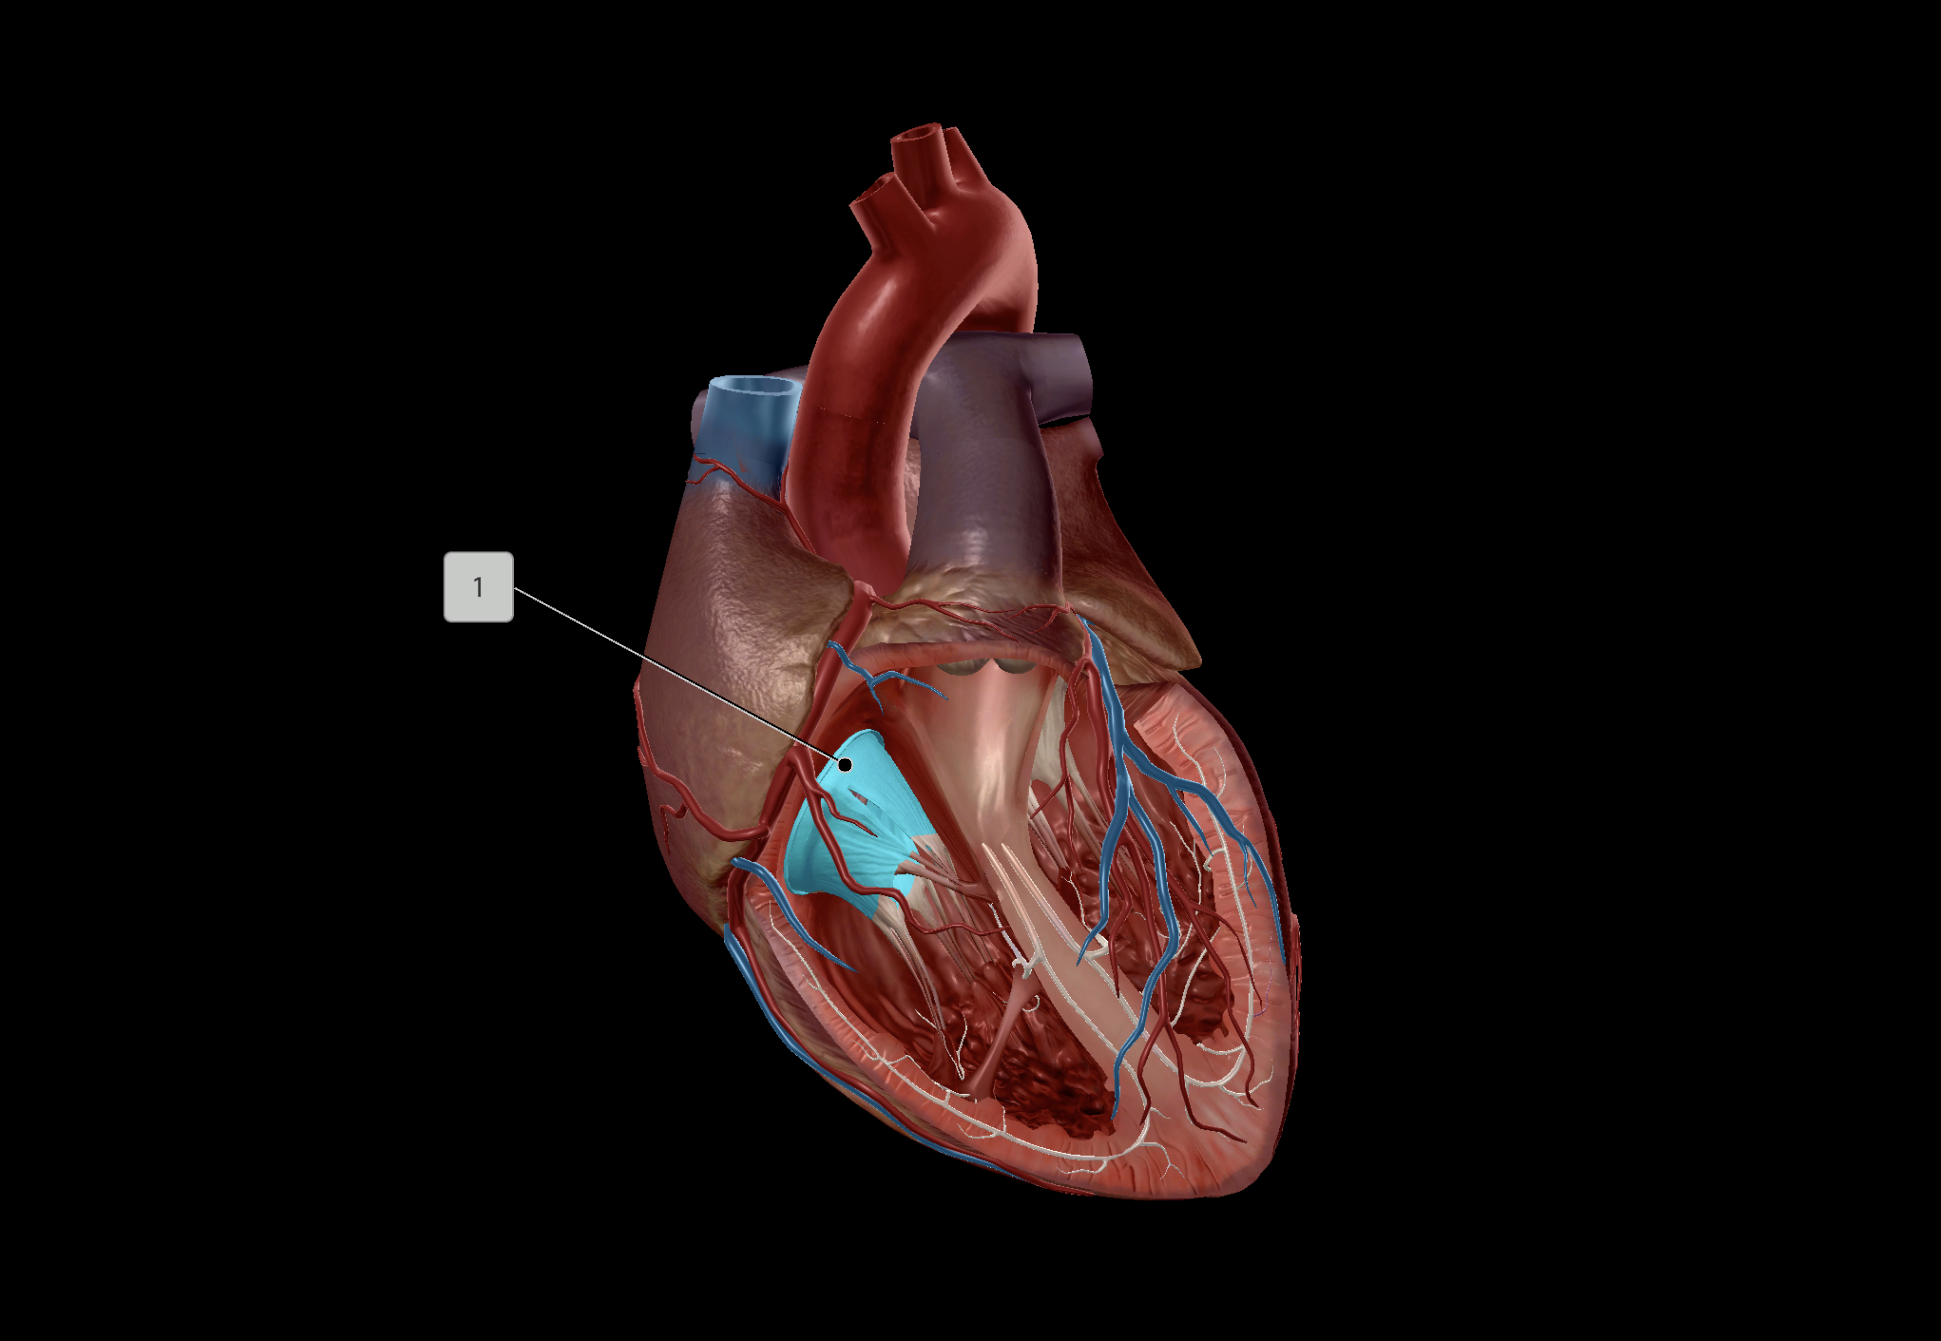

Tricuspid Valve

Bicuspid Valve

Aortic Valve

Papillary Muscle

Pulmonary Valve

Interventricular Septum

Chordae Tendineae